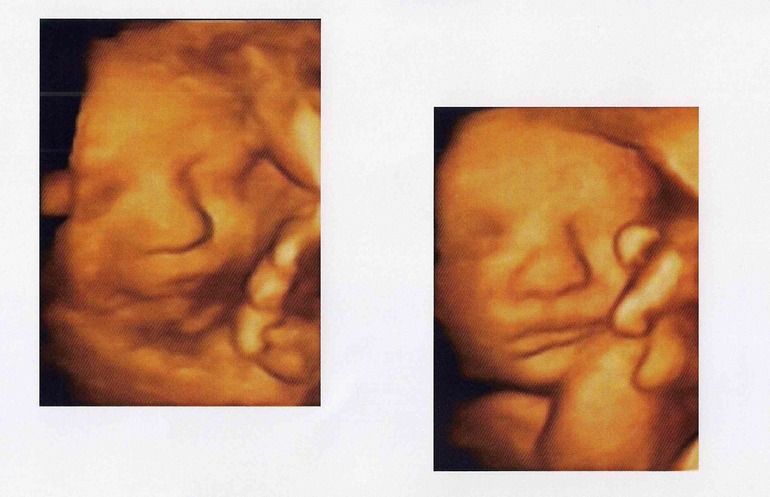

Ну и вот наши очередные фоточки с УЗИ в 36 полных недель. Пока не понятно что тут мамино, что тут папино